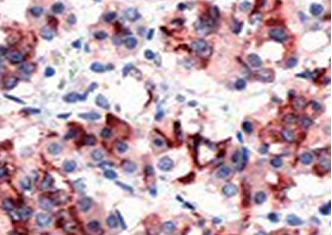

| 垂体瘤石蜡切片,用 PRL(GT2161)染色,细胞浆阳性,DAB 显色。 | ||

| 预处理:高pH热修复 | 阳性部位:细胞浆 | 阳性对照:胎盘/垂体瘤 |